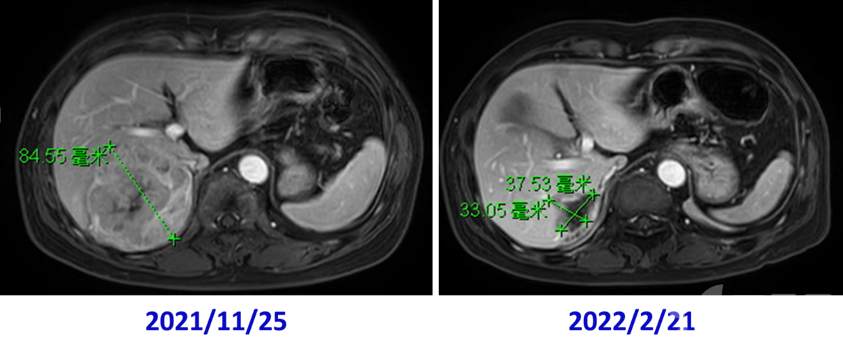

去年11月的一个肝癌患者,片子如上,外科医生第一反应肯定是切除,但是评估以后右半肝切除剩余肝体积不够,右后叶切除安全切缘不能保证(精准肝脏外科理念不但体现在术中,更要体现在术前规划阶段)。提请MDT讨论,用了PD-1+仑伐替尼+放疗降期治疗(放疗范围是右半肝,听放疗L教授说,不但可以控制肿瘤,还能促进左半肝体积代偿增生)。

12月底患者因心肌炎及甲状腺毒症再次入院,MDT讨论后停用免疫治疗,继续口服仑伐替尼降期。到了2月份再次评估,前后一对比明显好多了:

桃子熟了,该摘了。术前规划如下图,重点:肝脏右后叶切除并不能完全覆盖肿瘤,还有8段背侧段门脉分支供血,应该做右后叶+8段背侧段切除。